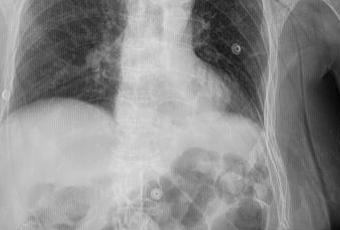

TÓRAX AP

LA PROYECCIÓN RADIOGRÁFICA OBTENIDA MUESTRA LOS SIGUIENTES HALLAZGOS:

Tejidos blandos simétricos, sin cambios en su densidad.

Silueta cardiomediastinica, con engrosamiento.

Botón aórtico, con calcificación.

Tráquea y columna vertebral central.

Hilios pulmonares, sin alteraciones.

Campos pulmonares, con patrón reticular difuso bilateral. Pulmón derecho, hacia lóbulo superior, probablemente en segmento III por topografía se observa imagen en anillo de sello, así como a nivel parahiliar inferior se observa imagen redondeada, irregular, bien definida, que mide 11 × 14 mm. Pulmón derecho, a nivel parahiliar existe imagen redondeada, irregular, bien definida, que mide 8 × 8 mm.

Senos cardio y costo frénicos bien definidos, sin identificar datos de derrame pleural.

A nivel de hombro derecho, con presencia de material de osteosíntesis. Resto de estructuras óseas, sin evidencia de lesiones líticas, blásticas o perdida de la contigüidad. Existen osteofitos marginales.

impresión diagnostica:

EN EL PRESENTE ESTUDIO RADIOGRÁFICO, CON IMÁGENES SUGERENTES DE NEUMOPATÍA CRÓNICA INTERSTICIAL, ASÍ COMO IMÁGENES SUGERENTES DE ADENOPATÍAS PARAHILIAR BILATERALES VS NÓDULOS PULMONARES, SIENDO LA DE MAYOR TAMAÑO DE LADO DERECHO.

MATERIAL DE OSTEOSÍNTESIS A NIVEL DE HOMBRO DERECHO.

ATEROESCLEROSIS Y CAMBIOS OSTEODEGENERATIVOS.